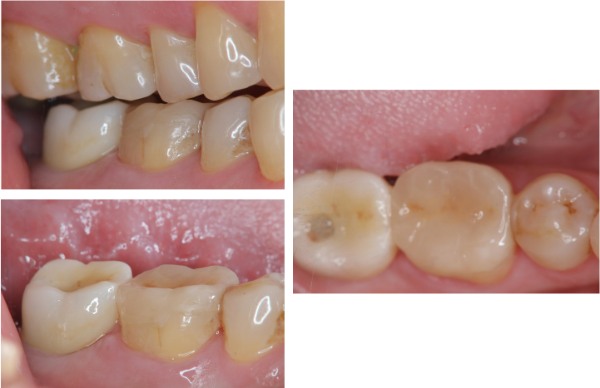

治療前,二次蛀牙,咬頭受損

蛀牙未到牙髓

冠塊體體製備

術前、術後比較